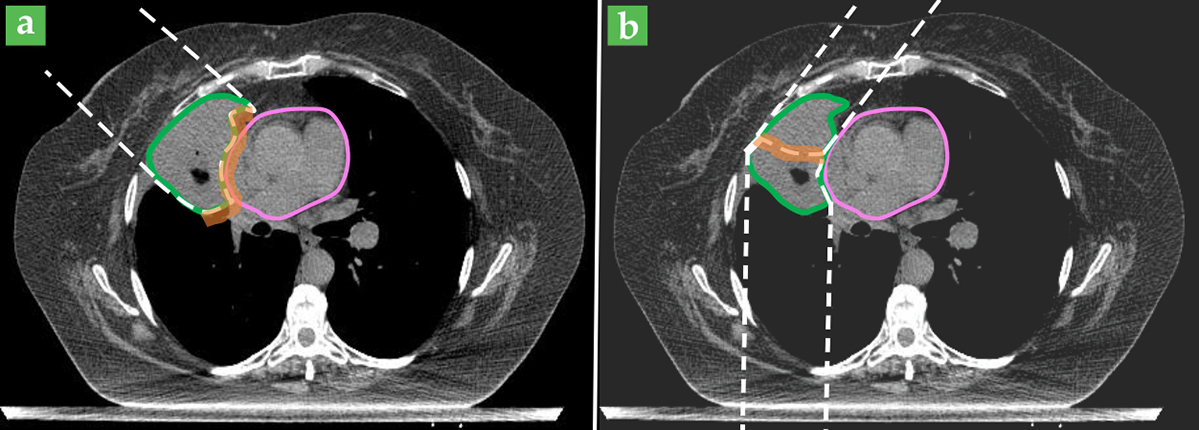

As an example, consider a patient being treated for a lung tumor adjacent to the heart, as shown in figure 1. If there were no uncertainty in the beam range, the ideal treatment plan would be to use a single beam incident from the side and stopping at the deepest edge of the tumor adjacent to the heart, as shown in figure 1a. However, that arrangement would never be used, because the beam-range-uncertainty margin would include part of the heart, and the full radiation dose may do severe damage to that critical organ. Instead, nonideal beam arrangements such as the one in figure 1b are routinely used to avoid shooting the beam directly at the heart. As a result, the tumor can be fully treated and the heart is spared from high doses, although one of the treatment beams now passes through the lung. The low to intermediate doses thereby delivered to the healthy lung tissues can also have long-term implications for the patient’s health. But the patient has two lungs and only one heart, so the risk of lung damage is regarded as more acceptable.

Figure 1. For a lung tumor (outlined in green) abutting the heart (pink), the ideal treatment plan (a) would use a single proton beam (outlined by dashed white lines) that stops at the deepest edge of the tumor. Due to the beam-range uncertainty, however, a margin (orange shaded area) must be added to the treatment area targeted for the full prescribed radiation dose. The end of the beam range is thus inside the heart, which may suffer severe damage or functional complications. To avoid such risk to critical organs, a suboptimal plan (b) with two beams might be used instead, even though it now delivers a low to intermediate radiation dose to the healthy lung.